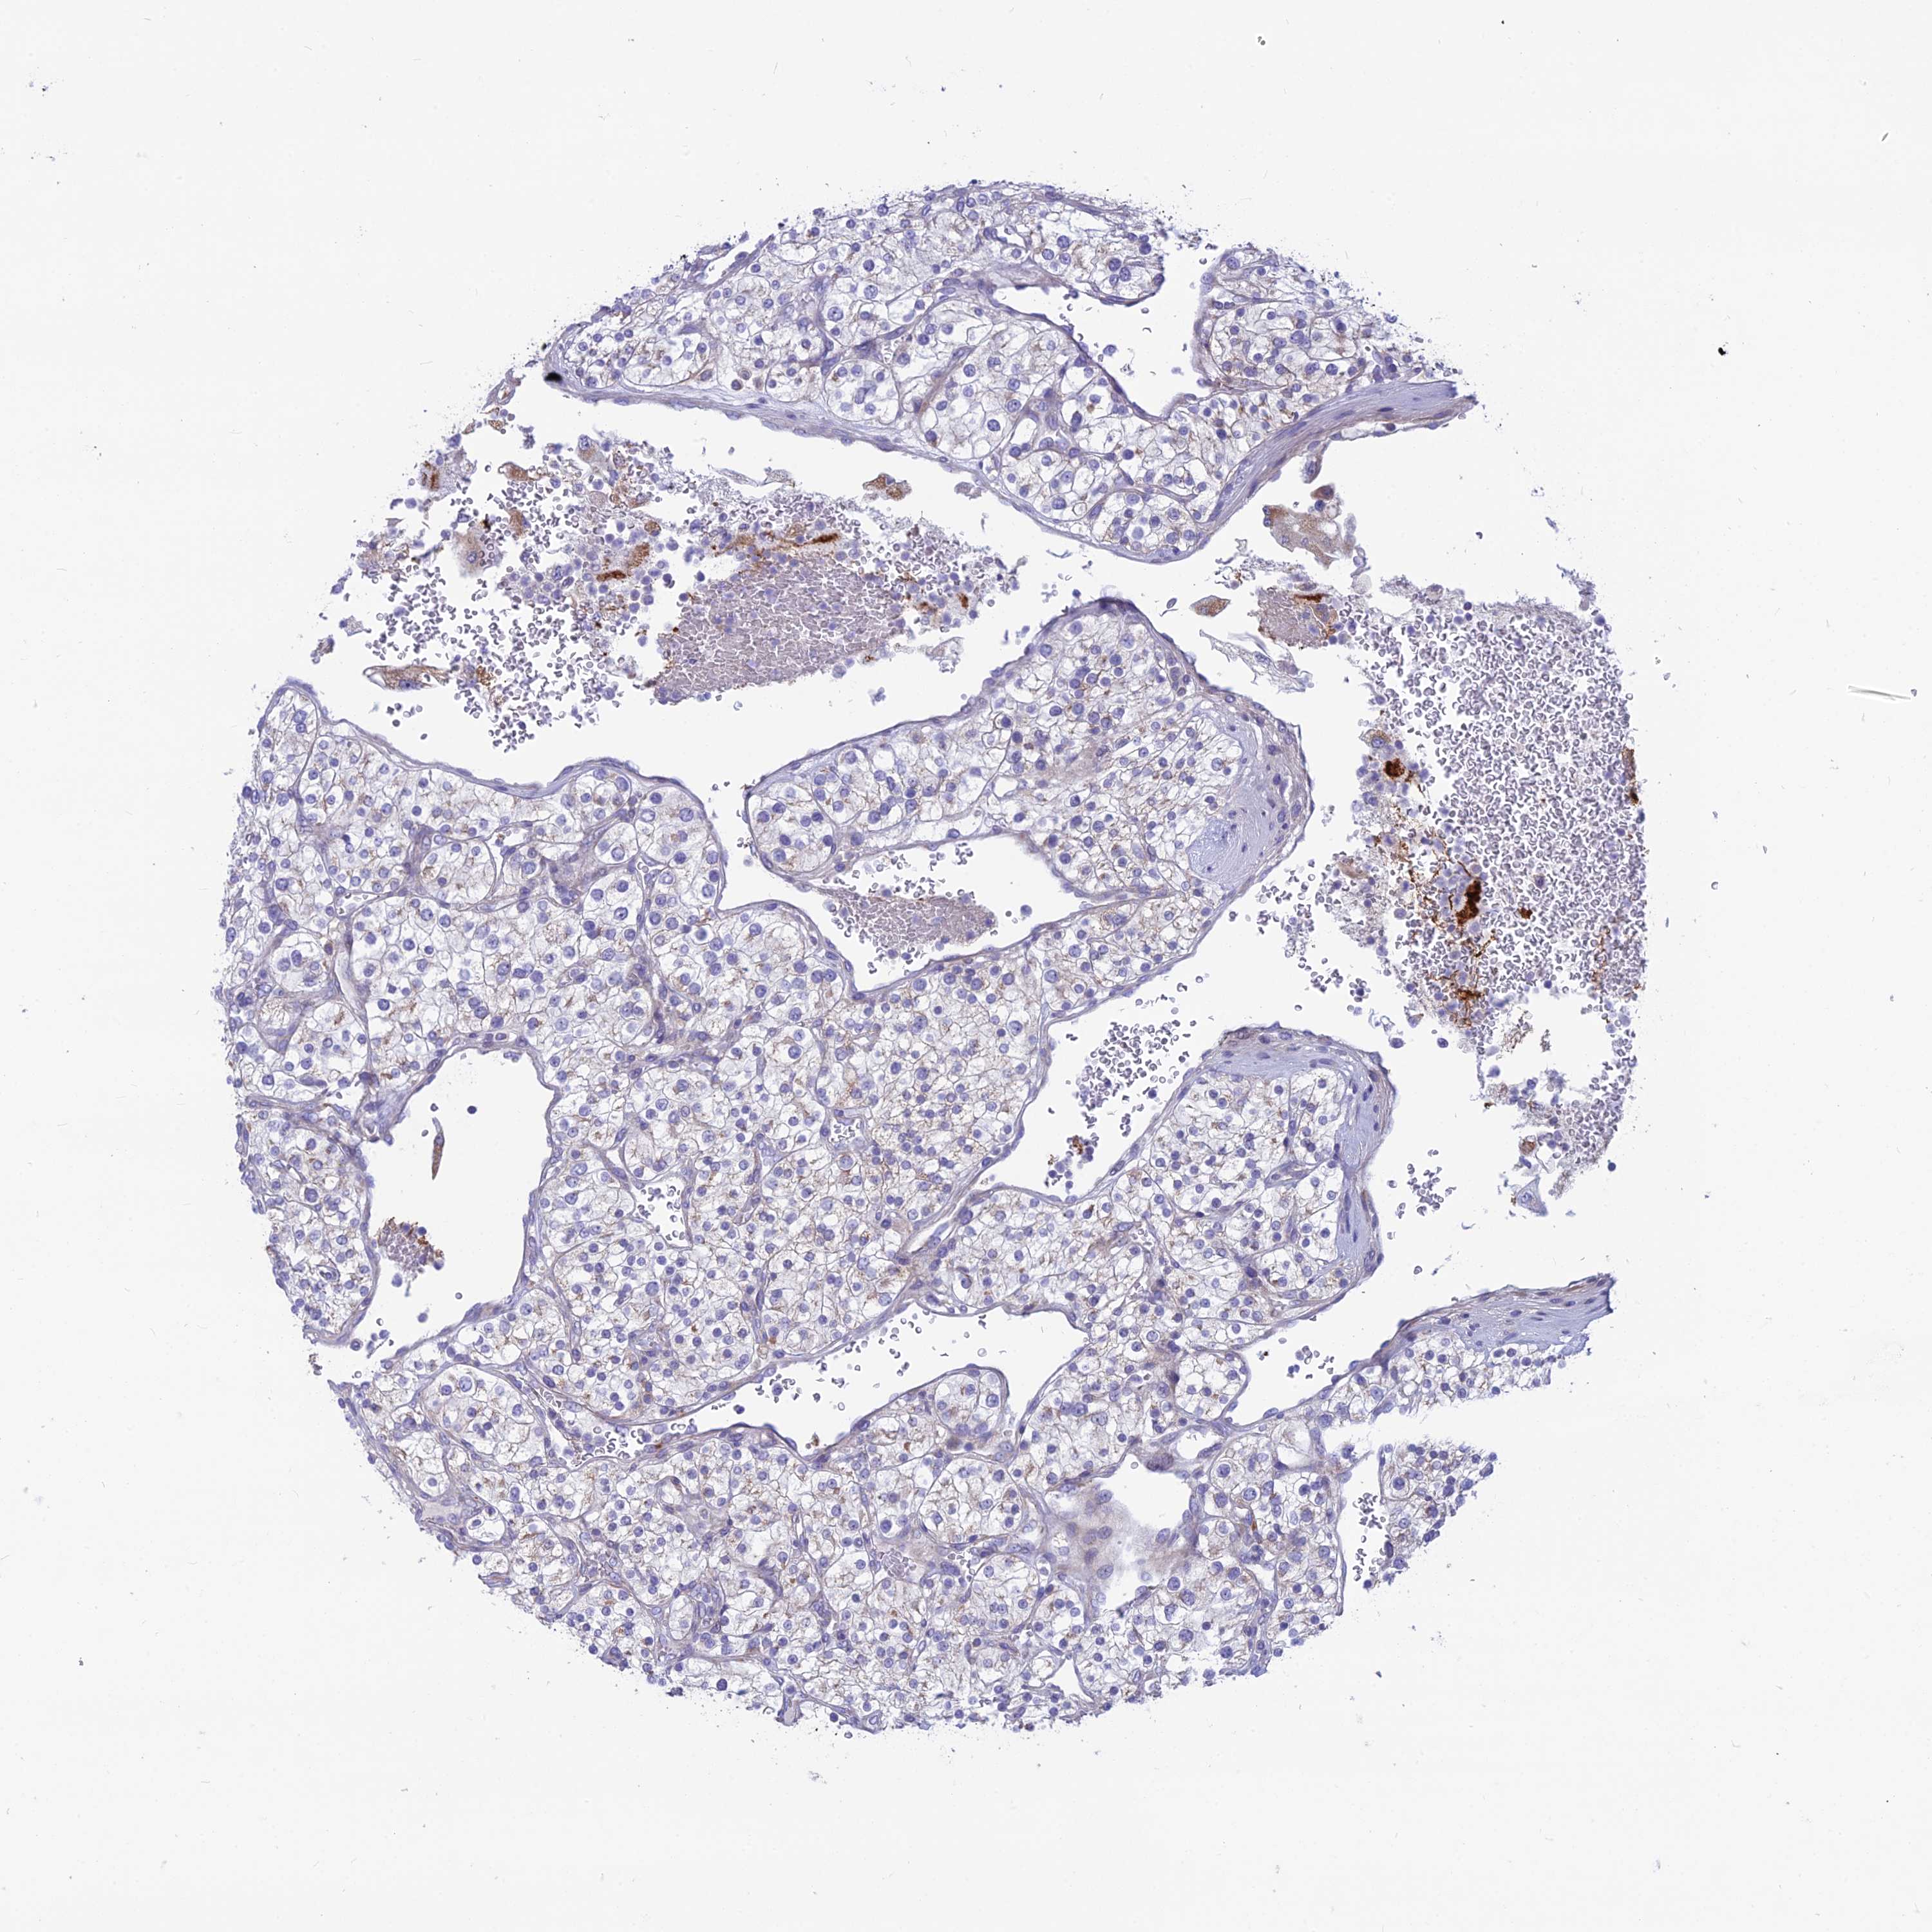

KIDNEY RENAL PAPILLARY CELL CARCINOMA (TCGA) - Interactive survival scatter ploti

The Survival Scatter plot shows the clinical status (i.e. dead or alive) for all individuals in the patient cohort, based on the same data that underlies the corresponding Kaplan-Meier plots. Patients that are alive at last time for follow-up are shown in blue and patients who have died during the study are shown in red.

The x-axis shows the expression levels (FPKM) of the investigated gene in the tumor tissue at the time of diagnosis. The y-axis shows the follow-up time after diagnosis (years). Both axes are complimented with kernel density curves demonstrating the data density over the axes. The top density plot shows the expression levels (FPKM) distribution among dead (red) and alive patients (blue). The right density plot shows the data density of the survived years of dead patients with high and low expression levels respectively, stratified using the cutoff indicated by the vertical dashed line through the Survival Scatter plot. This cutoff is automatically defined based on the FPKM cutoff that minimizes the p-score. The cutoff can be changed by dragging the vertical line or by entering a cutoff value in the square labeled "Current cut-off".

Under the Survival Scatter plot the p-score landscape (black curve; left axis) is shown together with dead median separation (red curve; right axis). Dead median separation is the difference in median mRNA expression between patients who have died with high and low expression, respectively. It is calculated as follows: median FPKM expression of dead patients with high expression - median FPKM expression of dead patients with low expression. This is intended to aid the user in visually exploring custom cutoffs and the associated p-scores and dead median separation.

Individual patient data is displayed and can be filtered by clicking on one or more of the category buttons on the top of the page. Categories describing expression level and patient information include: high, low, alive, dead, female, male and tumor stages. The scale of the x-axis can be toggled between linear and log-scale by clicking on the "x log" button. Mouse-over function shows TCGA ID, patient information and mRNA expression (FPKM) for each patient.

& Survival analysisi

Kaplan-Meier plots summarize results from analysis of correlation between mRNA expression level and patient survival. Patients were divided based on level of expression into one of the two groups "low" (under cut off) or "high" (over cut off). X-axis shows time for survival (years) and y-axis shows the probability of survival, where 1.0 corresponds to 100 percent.

PLAC9 is not prognostic in Kidney Renal Papillary Cell Carcinoma (TCGA)